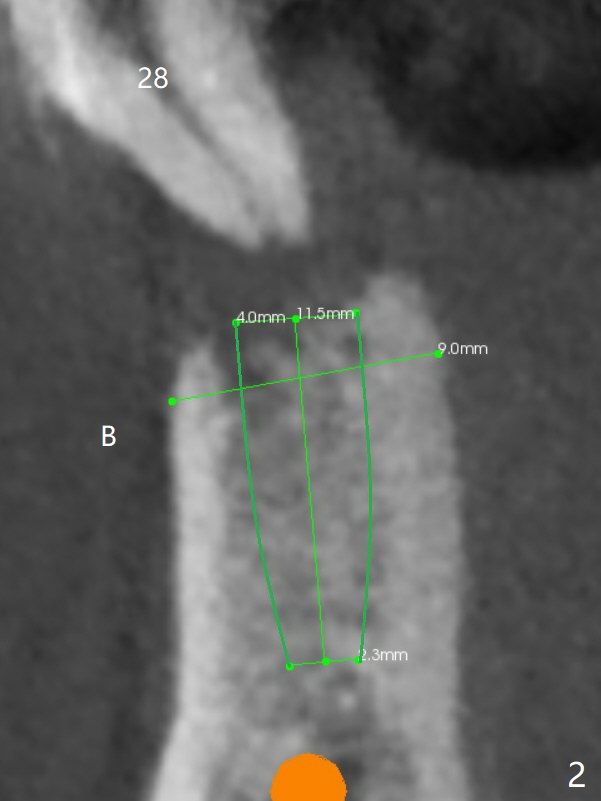

A 46-year-old man has finished upper implant placement (9-11 15 UR provisional) and wants to have lower anterior done (Long Cuff Wax up 2). The tooth #28 has exfoliated, while #22-27 FPD has mobility. It appears that the anchor tooth #22 has more severe periodontitis than that of #27. If the condition remains the same, section FPD between #22 and 23. Implants will be placed probably at #23, 26, 27 and 28. If both of the anchor teeth are non-salvageable, the possible implant will be at #22, one incisor, 27 and 28. In fact the patient requests an implant at #28.